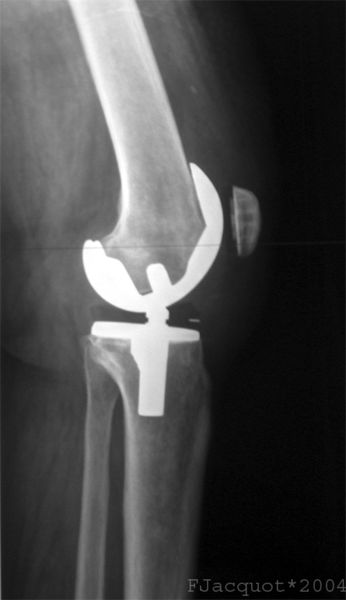

Total knee replacement has been performed for 50 years and is beneficial in a majority of cases and is "cost effective" in its improvement of quality of life issues, e.g., mobility and pain relief. Surgery aims to restore mechanical alignment while removing the source of the pain, thereby restoring a patient's activities of daily living. The use of TKR has increased annually and continues to expand as the population ages with heavier and heavier individuals. While other forms of arthritis may mandate TKR, osteoarthritis accounts for over 90% of cases, women being more likely to undergo surgery than men.

The indication for surgery remains radiographic changes and persistent pain limiting daily activity for more than six months despite maximal medical management. Despite hard markers, the decision to operate remains partially subjective because of individual perceptions, by physician and patient, of both pain and limitation. There are two further necessarily subjective considerations; patients must be considered acceptable surgical risks and able to participate in their aftercare.